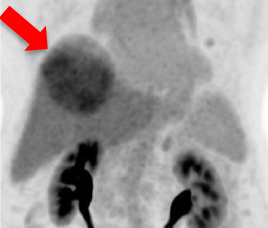

- 治疗前Tc MAA SPECT/ CT

- 预测肿瘤与非肿瘤钇90粒子分布

- 识别分流至肺部及内脏

- 使用鍀99m MAA(左)模拟钇90粒子分布(右)

- 评估治疗可行性

- 由双示踪剂正电子/电脑双融扫描计算处方剂量

99mTc MAA SPECT/CT Y-90 PET/CT